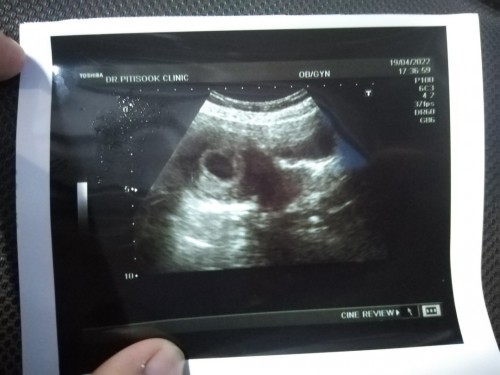

ตรวจเจอ2ขีดตอนวันที่9 เมษา 65วันนี้ลองไปซาวด์ดูอายุครรภ์เพราะไม่แน่ใจว่าอายุครรภ์กี่เดือนแล้วแต่คุณหมอบอกว่าไม่เจอเด็กอาจจะเป็นท้องเทียมแบบนี้แปลว่าไม่มีน้องไหมค่ะ

หมายถึงท้องลมค่ะ ต้องดูว่าอายุครรภ์กี่สัปดาห์แล้ว

ทำใจอย่างเดียวค่ะ ลองค้นในกุเกิ้ลดูนะคะว่าท้องลม แต่นับจากประจำเดือนแม่แล้วน่าจะประมาณ6สัปดาห์ อายุครรภ์ยังน้อยอยู่น่าจะมีหวังนะค่ะลองเปลี่ยนที่ชาวดูก็ได้ค่ะ ถ้าเป็นท้องลมจะมีเลือดออกและปวดท้องมาก เคยท้องลม2ครั้งค่ะ